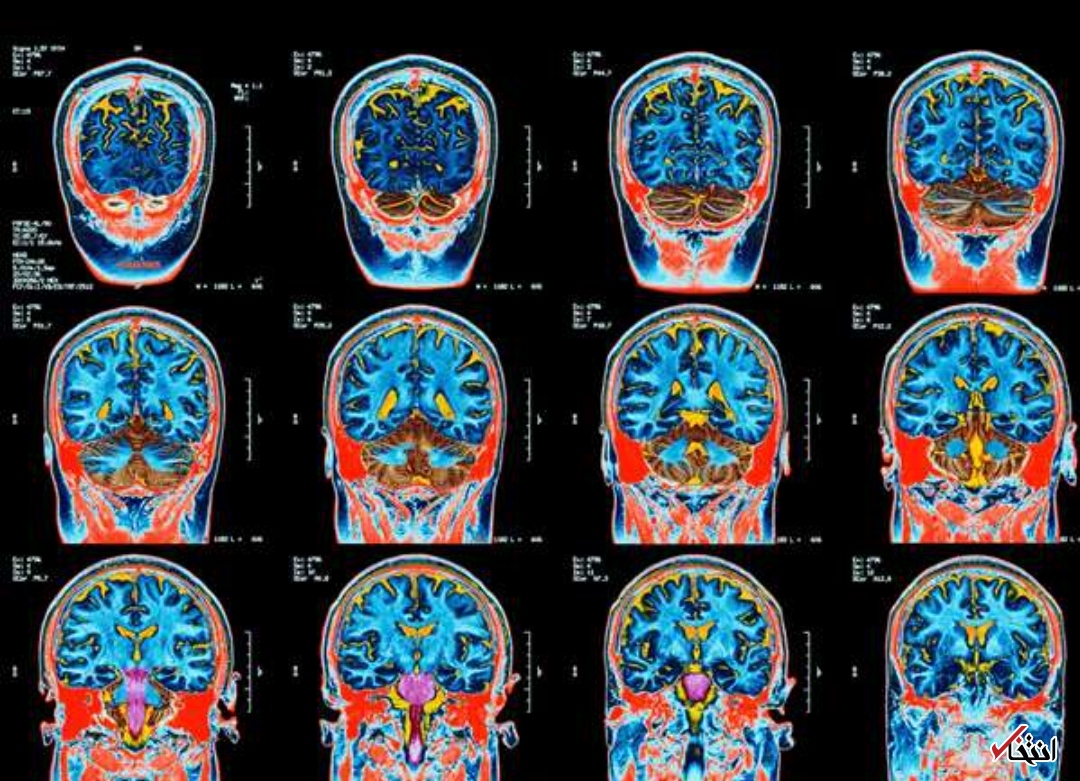

به گزارش سرویس خواندنیهای انتخاب، این بیماری ناشناخته مغزی باعث توهم، از دست دادن حافظه، اسپاسم، تحلیل رفتن عضلات و خرد شدن دندانها میشود.

حداقل ۴۳ نفر در استان نیوبرانزویک کانادا به دلیل این بیماری ناشناخته مغزی که باعث اسپاسم، از دست دادن حافظه و توهم میشود، بیمار شده اند و پزشکان را سردرگم کرده اند. مقامات بهداشت عمومی معتقدند از زمان مشاهده اولین مورد در سال ۲۰۱۵، پنج نفر از افراد در اثر این بیماری جان خود را از دست داده اند.